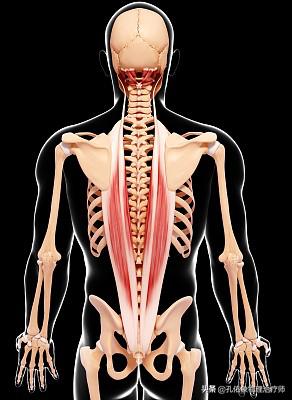

Nous pouvons imaginer que le disque humain ressemble à une gelée, les deux étant de forme similaire, avec une structure gélatineuse et collante au centre, entourée d'une couche externe d'anneau solide et mobile. L'image ci-dessus montre un disque intervertébral humain normal.

L'image ci-dessus illustre le fait que nos disques intervertébraux sont soumis à des forces différentes dans des positions différentes. Pour être plus précis et spécifique, la petite gelée (nucleus pulposus) est soumise à une pression asymétrique agissant sur le disque. Lorsque l'on se penche, la pression exercée sur le nucleus pulposus le pousse vers l'arrière, et lorsque le corps est incliné vers l'arrière, le nucleus pulposus est poussé vers l'avant, contrairement à ce qui se passe lorsque l'on se penche. Cela explique pourquoi la pression sur le nucleus pulposus n'est excessive que lorsque l'on se penche, ce qui entraîne une augmentation de la hernie. En position allongée, il n'y a pratiquement pas de pression et aucune modification de la proéminence n'est observée.

Deuxièmement, pendant la période de sommeil sur un lit dur, si vous n'avez pas besoin de faire de l'exercice dans la phase aiguë, mais dans la phase chronique, vous dormez simplement sur un lit dur, le manque d'exercice correspondant pour maintenir une certaine posture, rendra les muscles paraspinaux du dos à long terme.l'état d'adaptation raccourci.L'une des principales caractéristiques de cet état est que la structure tissulaire raccourcie empêche notre corps d'adopter une position plus confortable. Bien sûr, les patients ne le remarquent généralement pas, car notre corps est très doué pour trouver des mouvements compensatoires afin de compléter la posture souhaitée. Les tissus raccourcis entraînent un déséquilibre local dans le corps et, avec le temps, dormir dans un lit dur devient de plus en plus douloureux.